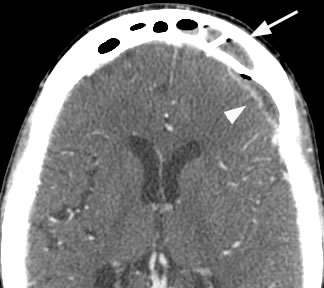

Axial post-contrast image shows arrowhead pointing to the peripherally enhancing intracranial extra-axial fluid collection containing small foci of gas which communicates with the left frontal sinus disease marked by the arrow. This patient developed an epidural abscess related to his frontal sinus disease.